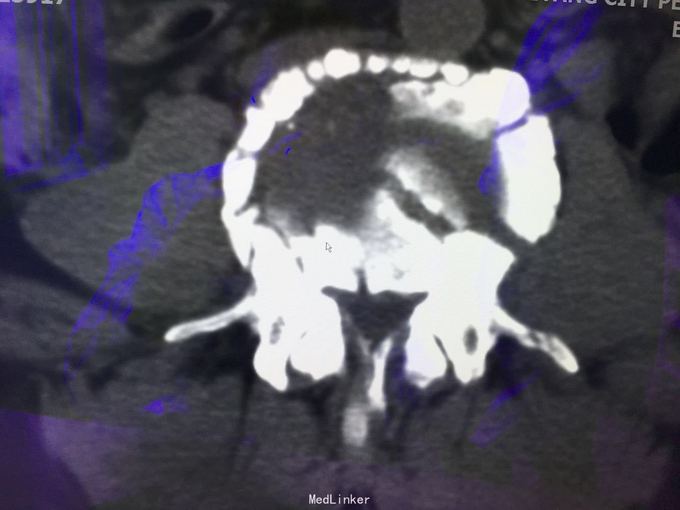

查体:左肾区叩痛,无皮肤隆起,未扪及肿块;腰椎压痛,活动受限,双下肢感觉存在,右小腿石膏托外固定,有踝关节明显肿胀,局部压痛活动受限,指端感觉血运可。 CT及X片:L2、L4椎体爆裂性骨折,L1-L4左侧横突骨折,右坐骨支骨折,右侧胫骨内、后及右侧腓骨外踝骨折,右足第1-4跖骨向外侧脱位及半脱位,伴近端斯脱性骨折。左肾挫裂伤,左肾重度积水,左肾周血肿。

诊断:右足lisfrance损伤,左肾挫裂伤;左肾周血肿,左侧输尿管结石伴左肾重度积水,L2、L4椎体骨折,L1-L4左侧横突骨折,右侧坐骨支骨折,右三踝骨折,全身多处皮肤软组织挫伤 处理:急诊行左肾探查,左肾切除术,择期行经后路腰2、4椎体骨折切开复位、椎公根螺钉内固定术+右内、外踝骨折切开复位内固定术,择期行右足lisfrance关节复位克氏针内固定术。